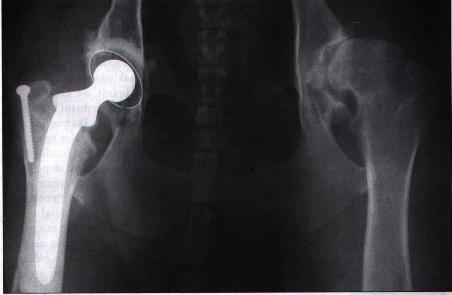

snížením funkčnosti kyčelního kloubu. Ve stadiu příprav (u nás) a

finančně náročnější je totální náhrada kyčelního kloubu, která se

zpravidla fixuje cementem. V této době je to nejpřijatelnější řešení

problémů doprovázejících dysplazii. Její provádění je u nás ale skutečně

Protéza kyčelního kloubu na RTG snímku

(Gutbrod, Norimberg v Svět psů 10/99: 24-25).

Vzhledem k pokročilé artróze tento pes před operací silně kulhal. Po zákroku bylo možno operovanou nohu zase bezbolestně zatěžovat. Později byl úspěšně vyměněn i druhý kyčelní kloub. |